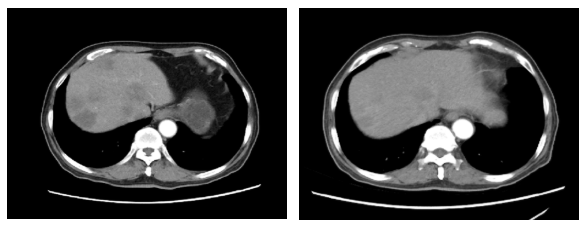

2019.11.18 腹部CT:肝脏多发结节(图2),考虑转移。

图2. 腹部CT(2019.11.18)

2020.1.5影像学评价:腹部CT:肝脏多发结节,较前增多增大,考虑进展(图3)。

图3. 腹部CT(左:2019.11.18,右:2020.1.5)